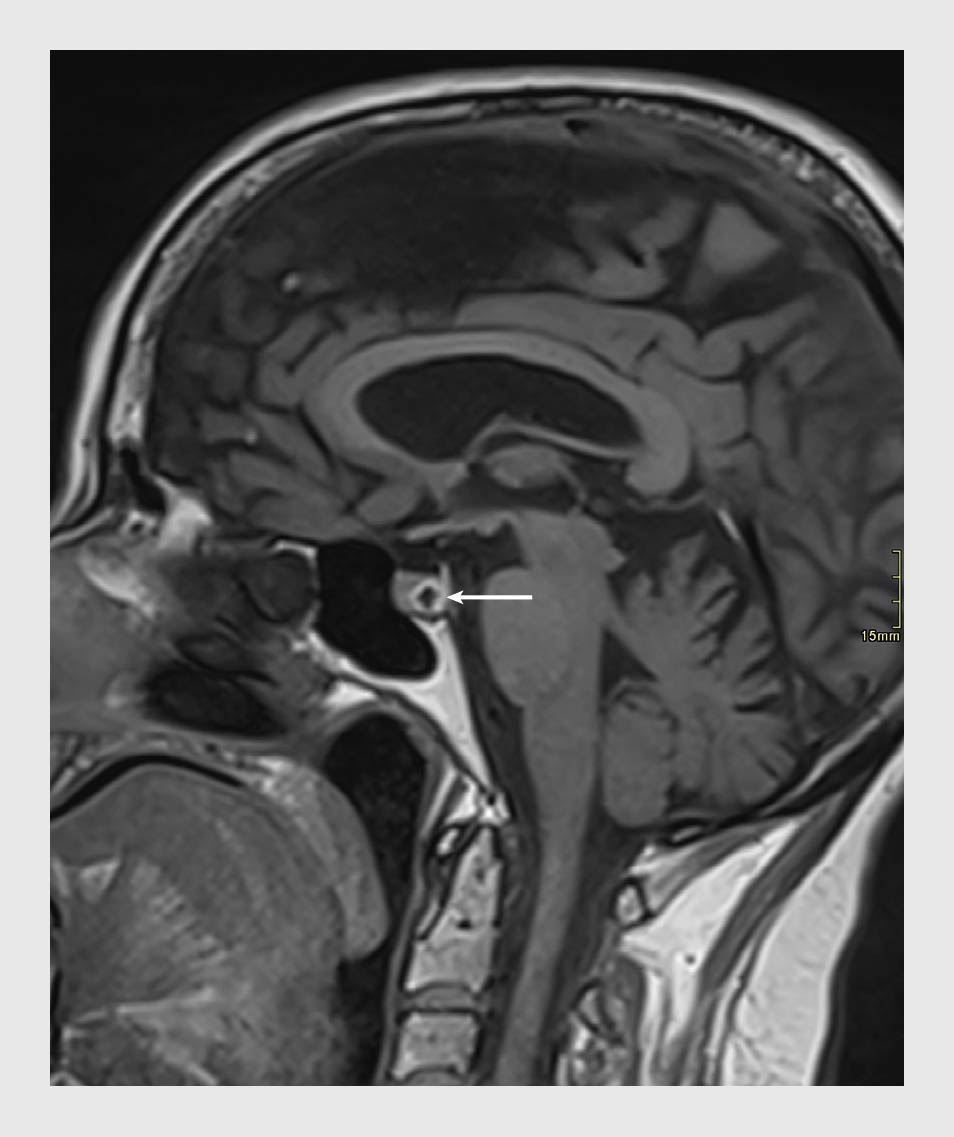

Een 78-jarige patiënte met in de voorgeschiedenis diabetes mellitus type 2, een herseninfarct en auto-immuunhypothyreoïdie kwam op de Spoedeisende Hulp vanwege plotselinge nystagmus, duizeligheid en braken, zonder visusverlies. Omdat de klachten acuut waren ontstaan en vanwege het eerdere herseninfarct verrichtten wij een CT-scan van de hersenen. De scan liet geen bloeding of nieuwe ischemische schade zien. Wij namen de patiënte op en er volgde een MRI-scan van de hersenen om eventuele vertebrobasilaire ischemie op te sporen. Op de MRI werd dorsaal in de sella turcica een hypofysesteen gezien, zonder aanwijzingen voor compressie op het chiasma opticum (figuur).